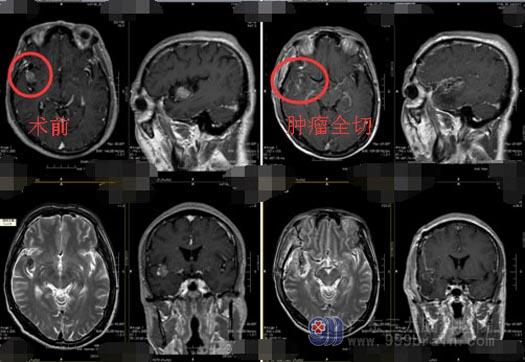

入科后完善各种检查,头颅MR示:右侧岛叶占位性病变,范围约1.6cm×2.6cm×1.9cm,考虑低级别胶质瘤(少突胶质细胞瘤或节细胞胶质瘤)可能性大,待排不典型脑膜瘤,CT血管成像显示右侧颞岛叶占位性病变及周缘存在少许小血管,病变紧贴右侧大脑中动脉M2段,为手术增加了难度。

经过缜密的讨论后,决定在术中采用唤醒麻醉,利用神经电生理技术精确定位脑重要功能区并探询病变与功能区的关系,最大限度地切除肿瘤并保留功能区的目的。由鲁明副主刀下为何叔行“右侧颞岛区脑膜瘤切除术”,术程顺利,术中见肿瘤位于大脑中动脉M2段上下干之间,肿瘤有钙化,血供丰富,予以镜下全切。